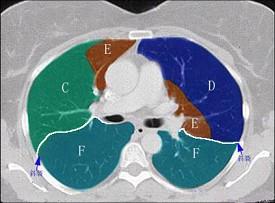

结合肺段模式心室层面(见图),选出右肺上叶的组成 ( )A、A+B+C+DB、A+B+C+D+EC、A+BD、A+B+CE、A

问题 结合肺段模式心室层面(见图),选出右肺上叶的组成 ( )

选项 A、A+B+C+D B、A+B+C+D+E C、A+B D、A+B+C E、A

答案 D